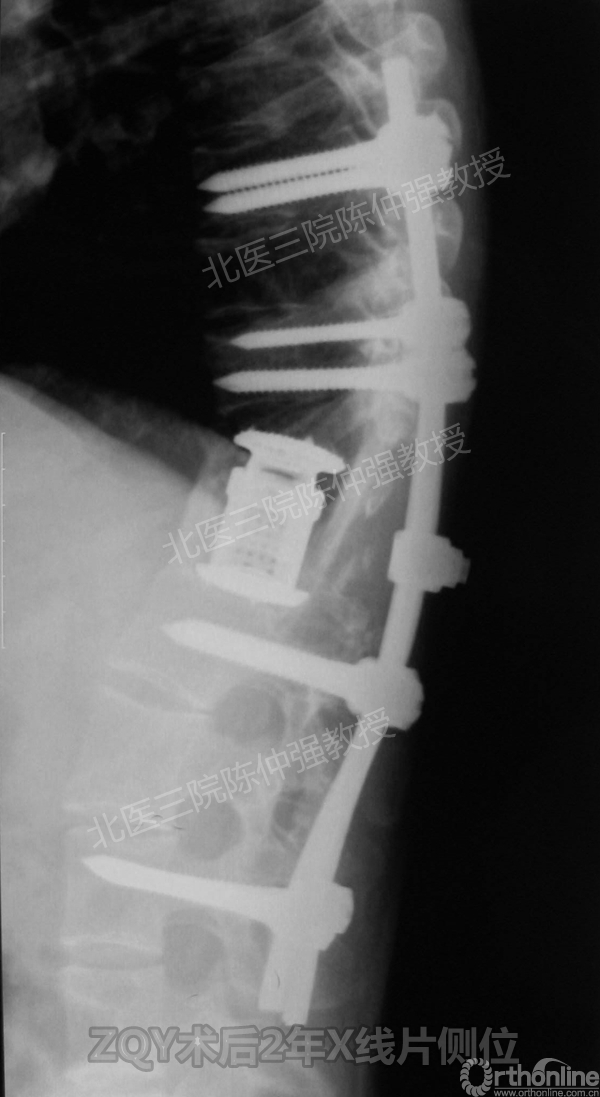

ZQY术后2年

ZQY术后5年

患者女性17岁,胸腰椎陈旧结核性侧后凸畸形,局部呈“麻花状”扭转,无神经功能受损表现。2005年,陈仲强教授带领团队实施后路+侧前方联合入路脊柱节段切除、双轴旋转矫形术。术后患者外观显著改善,神经功能正常。术后随访证实患者截骨矫形节段骨性融合良好,矫形效果持续良好。